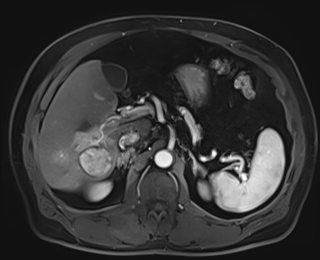

Case 3

20 F with PMH hypoplastic left heart s/p fenestrated Fontan procedure admitted for shortness of breath and hypoxia of uncear etiology.

145/58 mmHg / 78 bpm / 20 breaths/min / 97.6°F / 88% 6L

Faint expiratory wheezing in upper lungs, rhinorrhea, and congestion

AST 33, ALT 33, Alk Phos 222